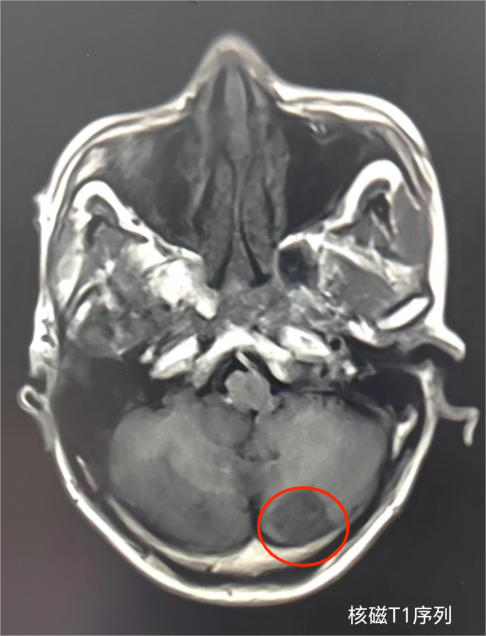

中风患者在我院影像科进行头颅核磁共振检查,发现小脑大面积急性脑梗死影像。